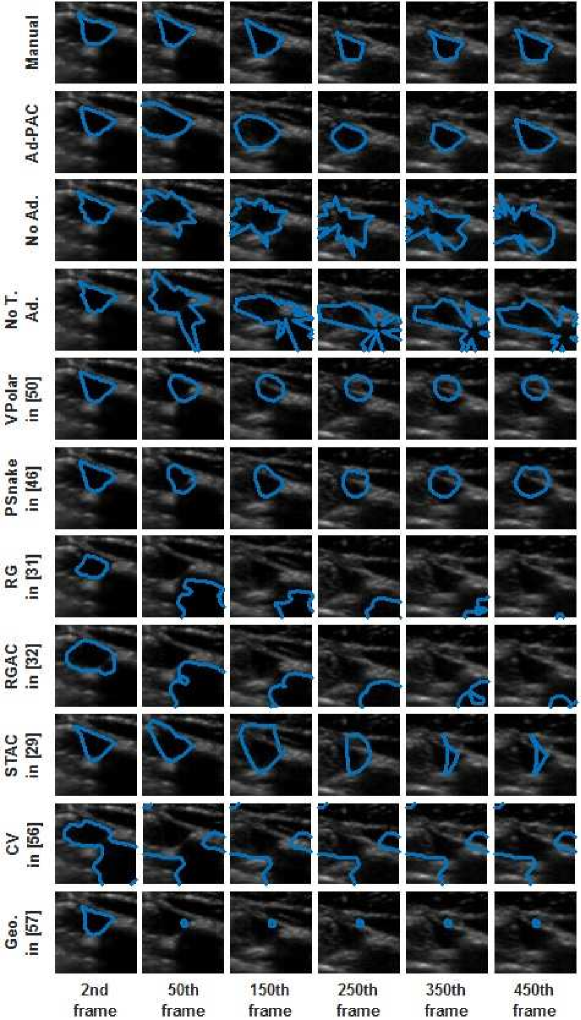

This Section compares the tracking performance of the proposed Ad-PAC algorithm with the manual segmentation and other algorithms as per section V for two sample video as shown in Figs. 12 and 13, respectively. From both figures, it is evident that the proposed Ad-PAC algorithm outperforms the existing algorithms and produces results very close to the manual segmentation. Further supporting evidence that parameter adaption significantly improves the performance is evident in rows 3 and 4 row of Figs. 12 and 13. The segmented contour is not smooth without parameter adaptation (which is observed as spikes) suggesting that the weight given to the curvature energy term was not sufficiently large enough to compete with the other energy terms and consequently, dominated by them.

Fig. 14 presents the DICE factors obtained from each algorithm, averaged across all 65 videos irrespective of IJV shape, intensity, speed of variation and quality. From this figure, it is clear that the proposed Ad-PAC algorithm outperforms all existing algorithms with its corresponding DICE factor greater than 0.64. Other algorithms perform significantly worse. In the following sub-sections, more detailed results are presented.